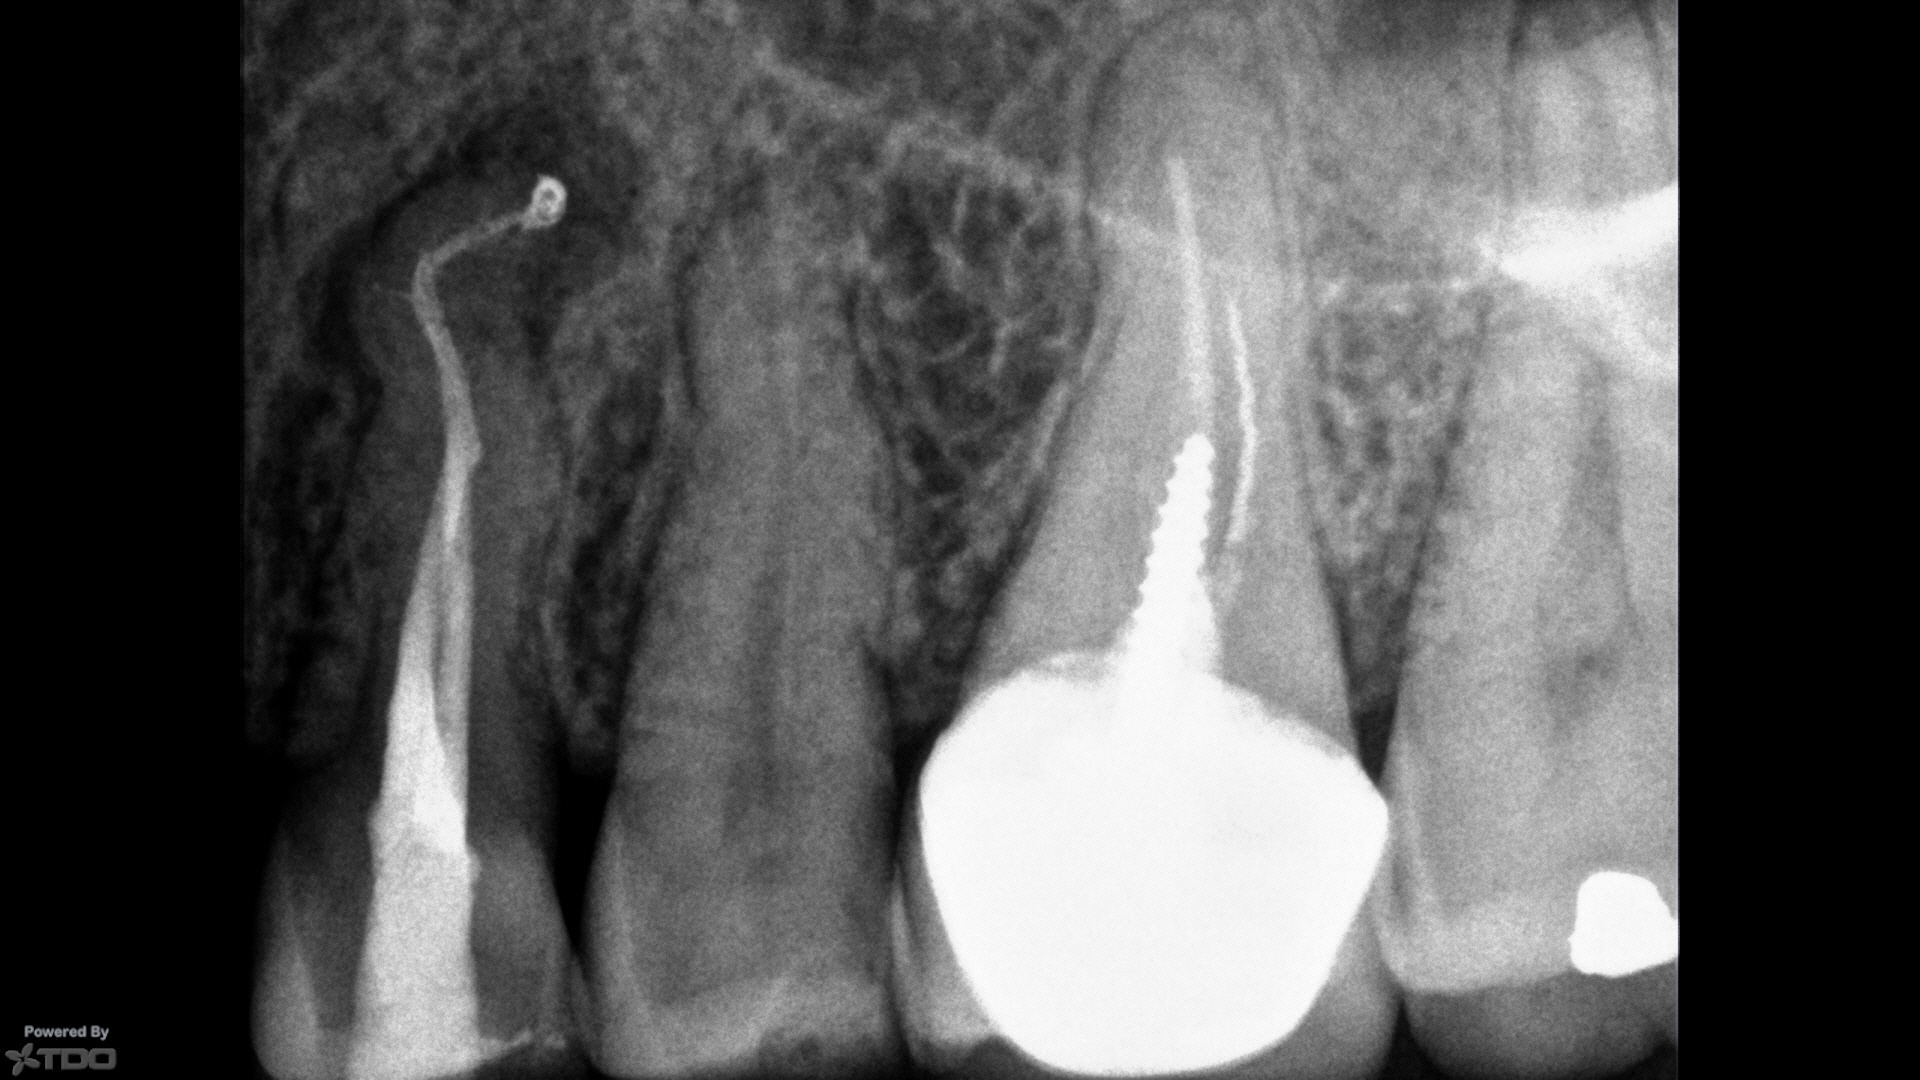

Le cabinet est spécialisé dans la prise en charge des pathologies de la racine dentaire. Nous réalisons exclusivement des soins endodontiques sur prescription : consultation diagnostique, traitement ou retraitement des canaux, chirurgie endodontique et suivi post-opératoire. Chaque soin est réalisé sous anesthésie locale, avec microscope opératoire, dans un environnement technique de haut niveau. Nous assurons également un lien étroit avec votre dentiste traitant pour garantir une continuité de soin optimale.

L’endodontie est la spécialité qui traite l’intérieur de la dent, notamment le nerf. En cas d’infection ou de douleur, elle permet de nettoyer, désinfecter et préserver la dent grâce à un traitement ciblé des racines. Ces soins précis sont réalisés sous anesthésie locale et microscope opératoire, dans un environnement strictement aseptisé.